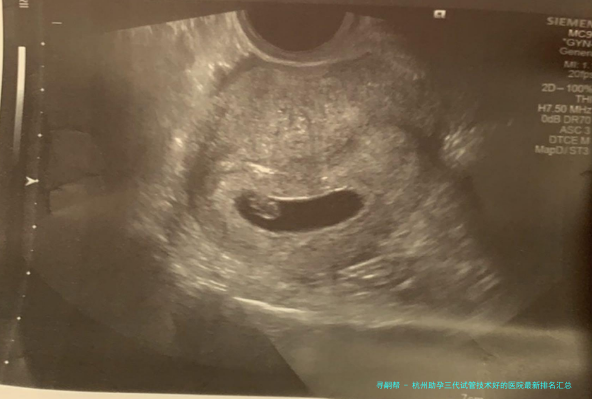

杭州优生医院配备了国际领先的助孕配备和设备,拥有出众的试管技术和配备。不论体外受精、胚胎移植还是其他辅助生育技术,该院均能提供高质量的服务。医院还时时引进国际前沿的试管技术和配备,维持技术层面上的领跑职位地方。